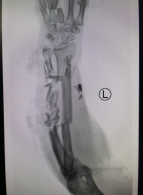

术前x光

周大爷就是因为在给机器填装玉米的时候,不小心整个左前臂被绞进机器,卡在机器内不能动,家人赶忙把机器拆了,这才把手拿出来,拿出来时整个前臂被绞的不成样,不住的出血,家人急打120,在家属强烈要求下送入我院。

手外四魏英华医生接诊后,看到如此严重的伤情,立即通知手术室做好手术准备,同时联系郑大伟主任及手术小组以最快的速度准备实施手术。

清理创面、剪去坏死的组织、固定骨折部位、吻合细如毛发的血管、缝合肌腱、对接神经,不敢有半点马虎和疏忽。时间一秒一秒地过去了,一根根血管在显微镜下完成吻合,忙碌了五个多小时,手术终于顺利结束。